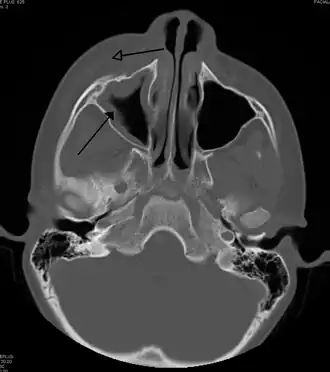

For cases of maxillary sinusitis, limited field CBCT imaging, as compared to periapical radiographs, improves the ability to detect the teeth as the sources for sinusitis. A coronal CT picture may also be useful.[60]

For sinusitis lasting more than 12 weeks, a CT scan is recommended.[66] On a CT scan, acute sinus secretions have a radiodensity of 10 to 25 Hounsfield units (HU). In a more chronic state, they become more viscous, with a radiodensity of 30 to 60 HU.[69]